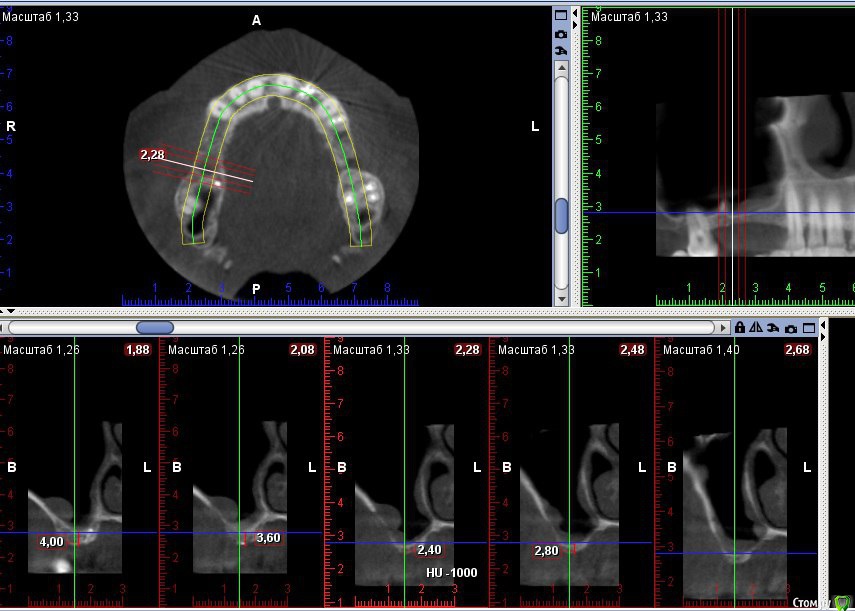

Kovalov Igor Опубликовано 19 мая, 2016 Поделиться Опубликовано 19 мая, 2016 (изменено) Здравствуйте уважаемые форумчане! Нужен совет по повторному синуслифтингу....3 месяца назад проводилась попытка синуслифтинга в 1 сегменте, отсутствие 14,15,16 зубов ... Разрез, формирование окна, в этом случае выбрал вход в синус с двух окон в проекции 14 и 16, получить перфу возле септы в области 16 когда отслаивал ... 14 отслойка без проблем... закрыл окна мембраной и ушил отправил погулять на 2,5-3 месяца.Вопрос как поступить ? Сделать одно большое окно? Как быть со спайками и как сложно их отделять ? Мембрану под перфу не подложил так как не делал ниразу этого... Кт после 3х месяцев ... Изменено 19 мая, 2016 пользователем Kovalov Igor Ссылка на комментарий

kriokov Опубликовано 19 мая, 2016 Поделиться Опубликовано 19 мая, 2016 пошел бы стандартно одним окном, да и первый раз думаю надо было одним окном идти, там не полная септа.Иногда приходиться остро работать на спайках как при расщеплении. Не знаю, но мне здесь одно здоровое окно видиться. И наверное зря Вы септу не спилили или не выкусили при первом заходе, если решили через три мес на повторный идти. Синус не плохо выглядит, думаю нормально все будет. 6 Ссылка на комментарий

kriokov Опубликовано 20 мая, 2016 Поделиться Опубликовано 20 мая, 2016 1 грамма мало на такой синус' даже крупного. 1,5 - 2 гр думаю 4 Ссылка на комментарий

red_butler Опубликовано 21 мая, 2016 Поделиться Опубликовано 21 мая, 2016 Куда вы 2гр L сыпите та? Тромбуете штоль?Даже еще раз пересмотрел срезы, Вы считаете что на такой операционной площади и при таком строении синуса расход будет меньше? 3 Ссылка на комментарий

Kovalov Igor Опубликовано 21 мая, 2016 Автор Поделиться Опубликовано 21 мая, 2016 Даже еще раз пересмотрел срезы, Вы считаете что на такой операционной площади и при таком строении синуса расход будет меньше?Ушло 2 грамма вы правы! ))) Спасибо всем за советы , ошибки были в первом случае малое и высоко расположенное окно, сделал в этот раз одно большое окно, спайки были только по периметру окна , было ощущение что окно начало заростать костью через три месяца, будто пластинка была поверх мембраны , может показалось ...Отслаивал до септы, графт 1,5 гр. в синус и 0,5 латерально от винтов и укрыл мембраной 25*25 владмива, мембрана не понравилась если честно ) Ссылка на комментарий